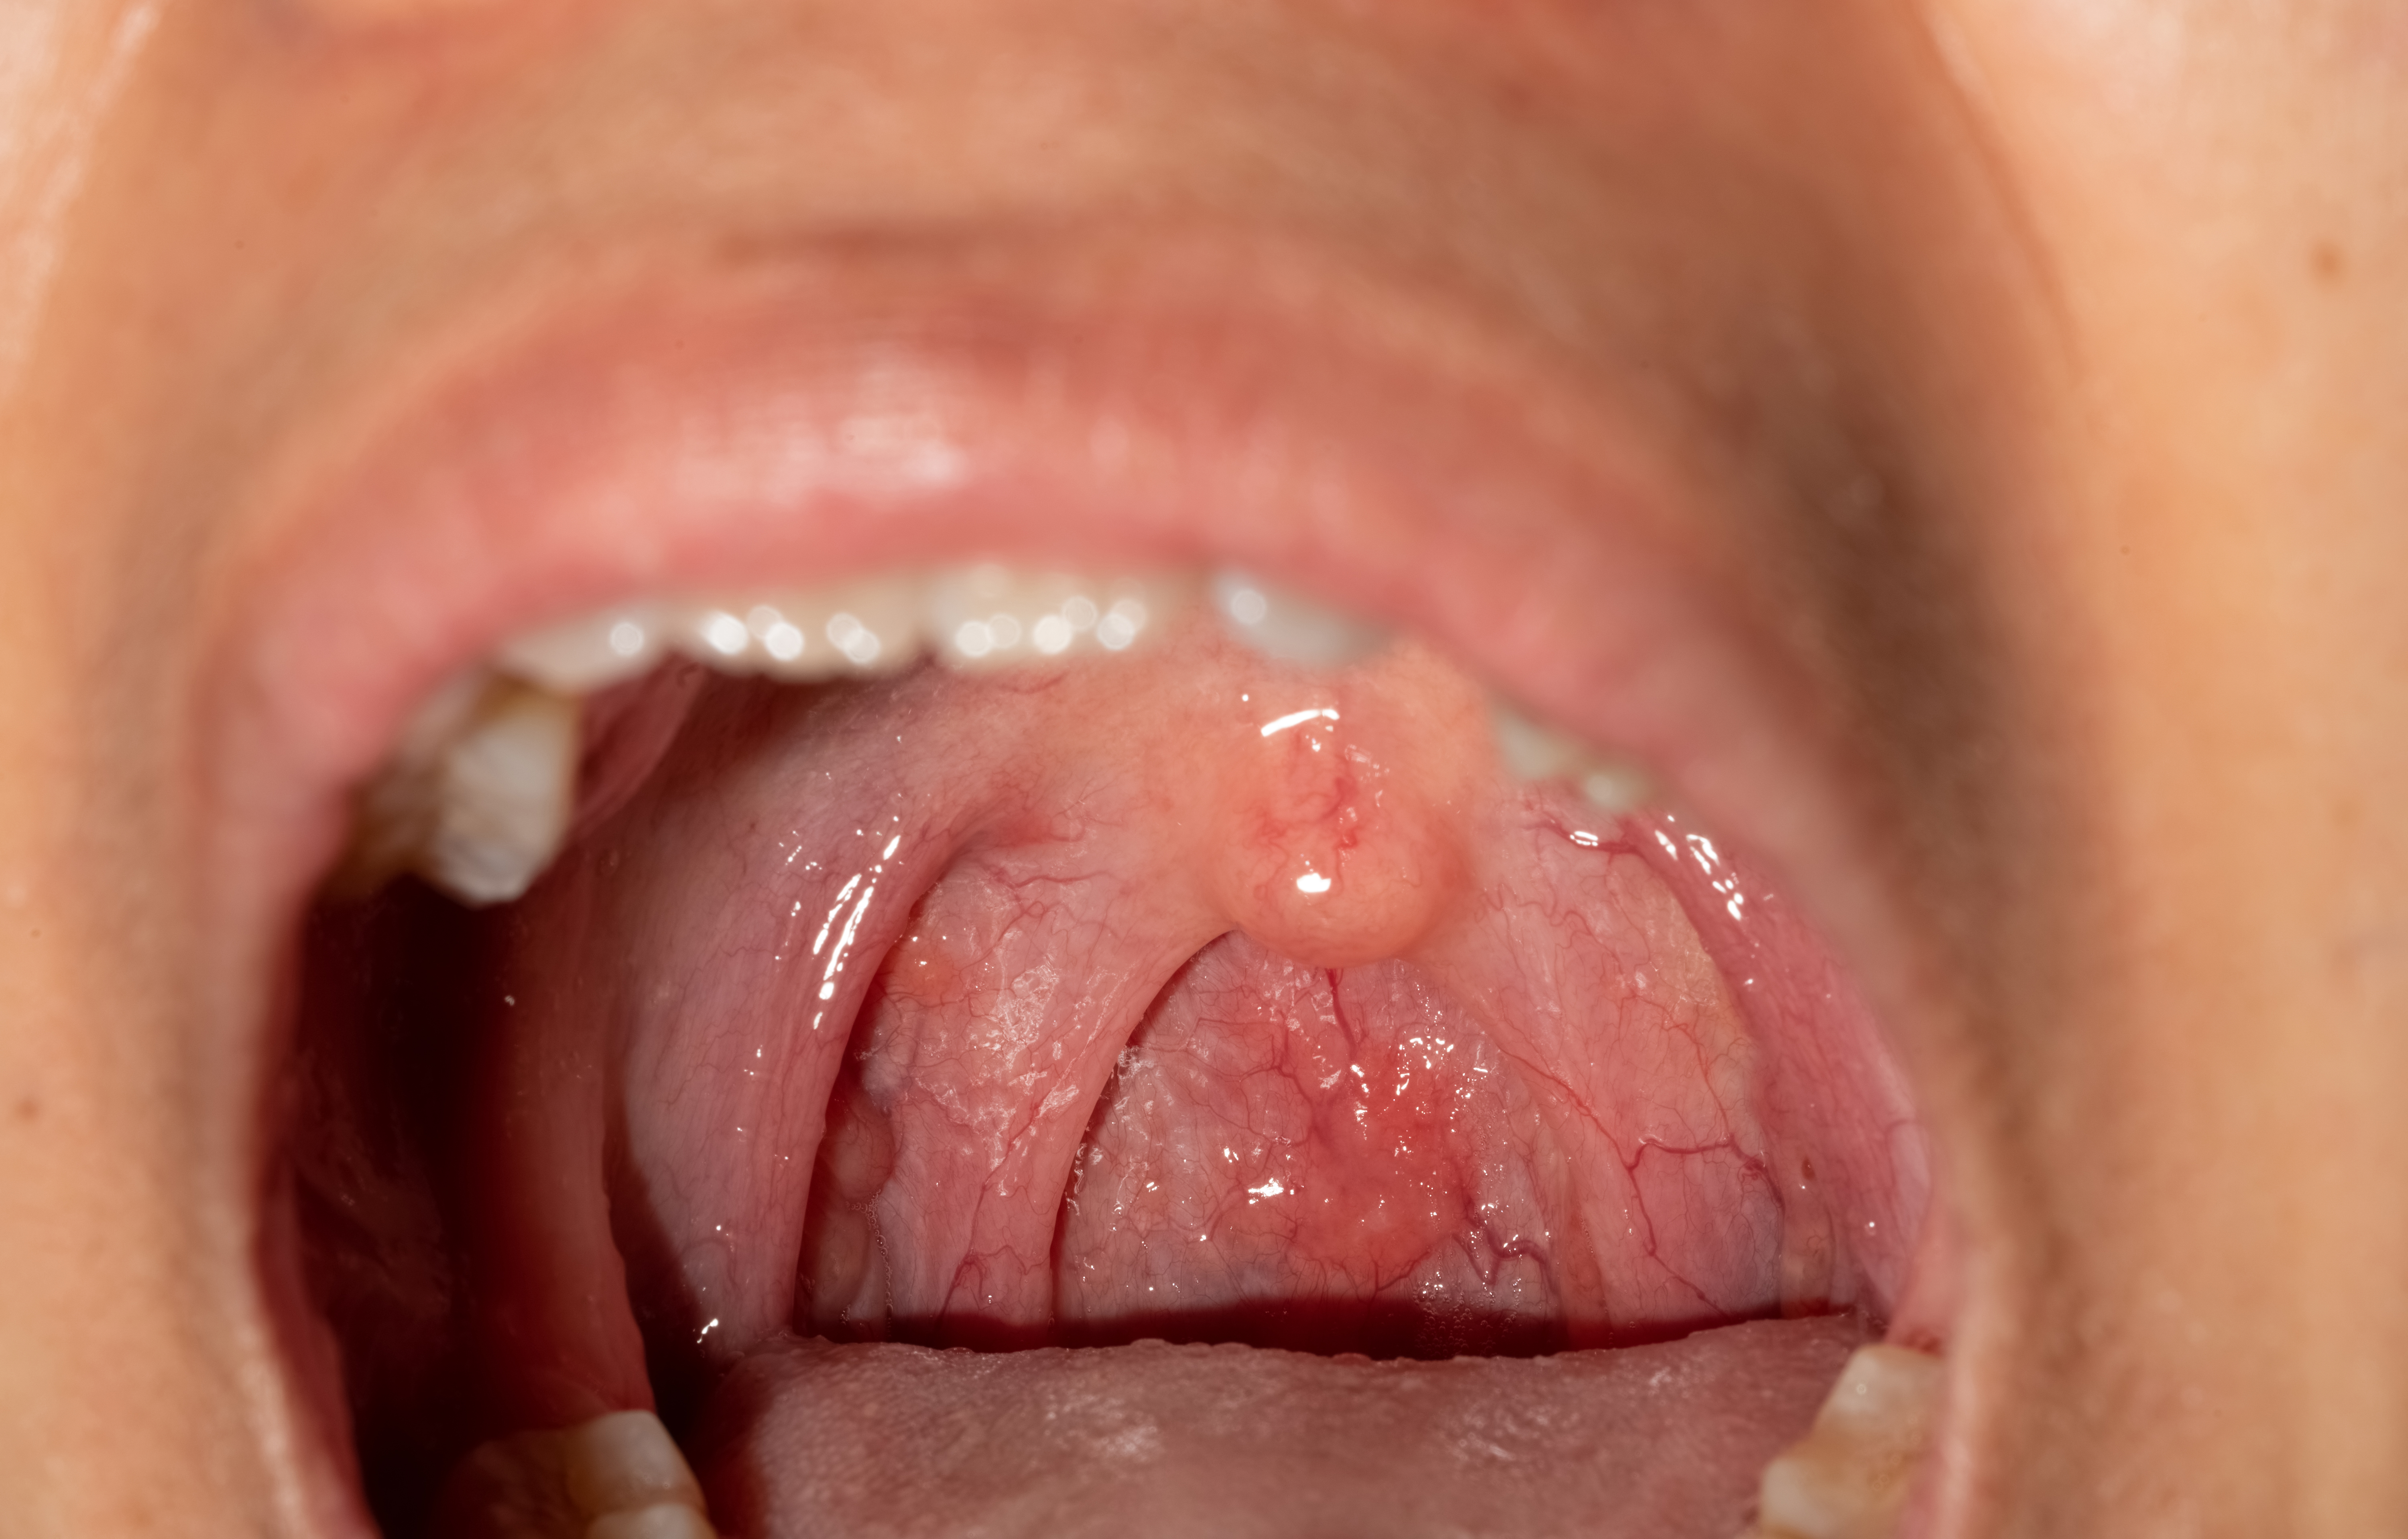

편도염이란 입안 양쪽 측벽 부분 즉 혀뿌리 부분의 하나씩 있는 구개편도에 염증이 생긴 질환으로 바이러스나 세균감염등의 의해 생기는 질환입니다. 흔히 편도염에 걸렸다고 할 때 급성 편도염을 의미하기도 합니다.

- 편도가 빨갛게 붓고 표면에 흰점이 군데군데 발생